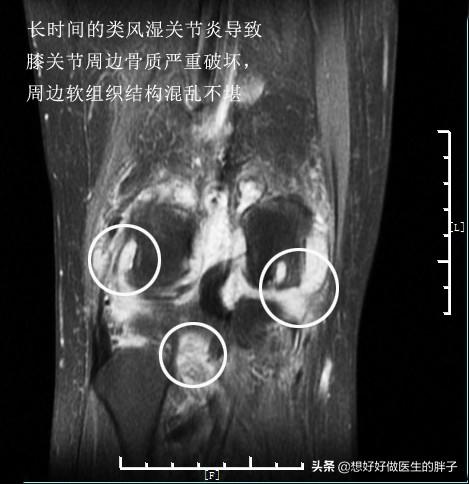

看起来这些病态的滑膜就像是魔鬼的触角一样恐怖,事实也是如此,尤其是对于类风湿关节炎以及痛风性关节炎的患者,这些滑膜会在关节内长久的存在,不断侵蚀关节的软骨以及骨骼。下图就是一例严重类风湿关节炎患者的核磁片子,他的关节软骨以及骨骼看起来已经像是被老鼠啃噬过一样了,这都归咎于类风湿滑膜炎的侵犯!

类风湿关节炎的病理基础就是关节腔滑膜的炎症,病理表现主要有滑膜衬里细胞增生、间质大量炎性细胞浸润,以及微血管的新生、血管翳的形成及软骨和骨组织的破坏等。